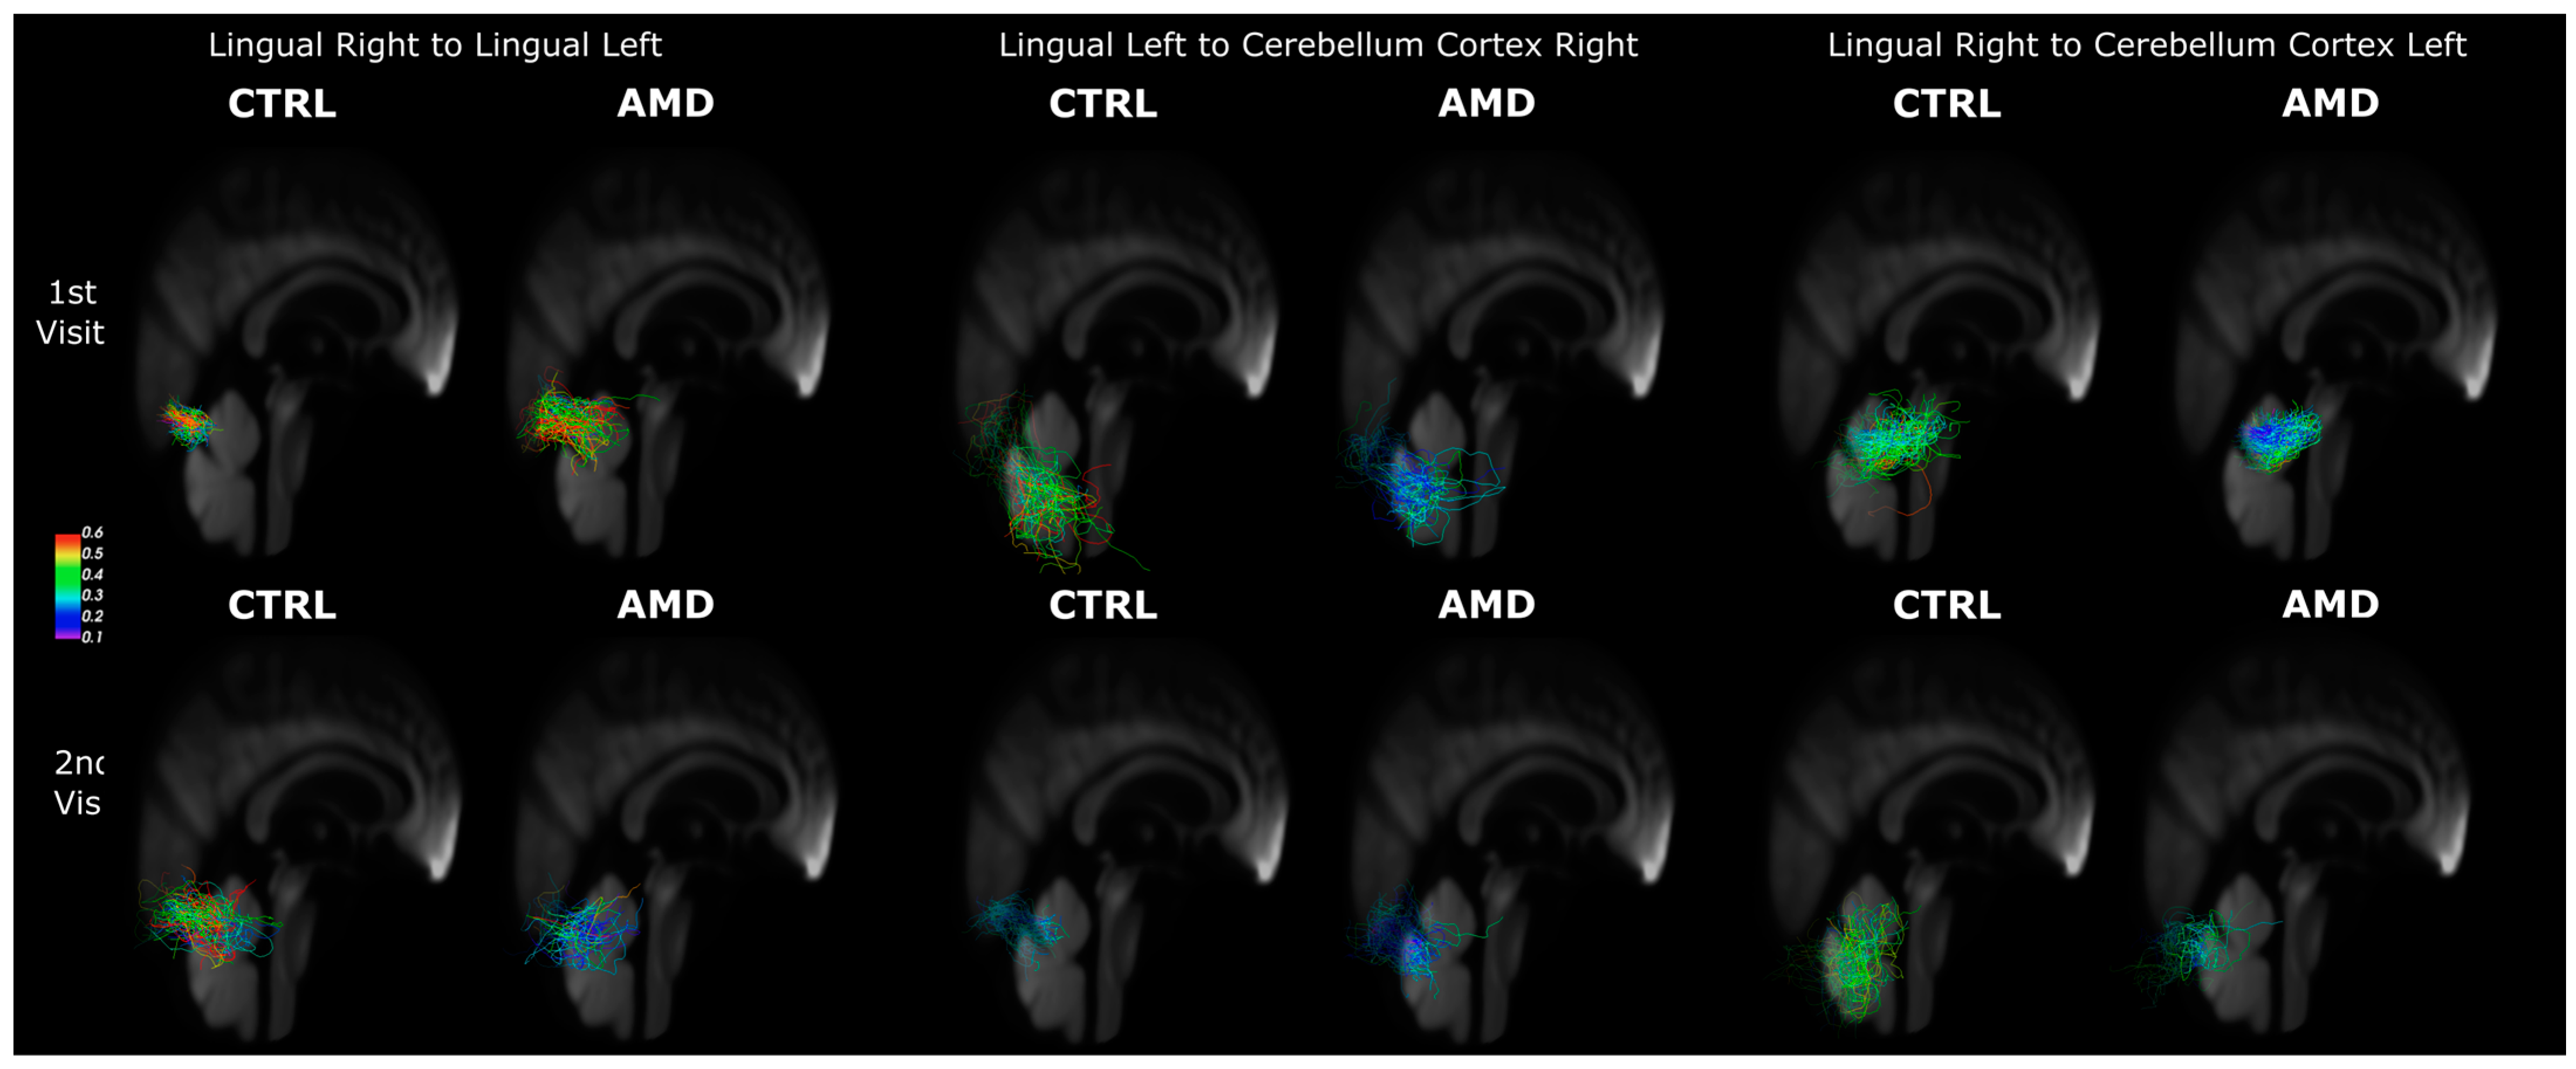

3.3. Connectivity Changes in AMD Participants